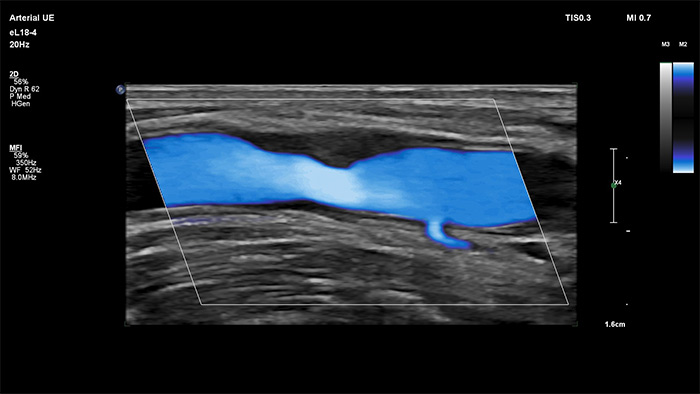

Philips MicroFlow Imaging wurde für die Erkennung langsamer und schwacher Blutflüsse in Gewebe entwickelt und verbessert bei Gefäßuntersuchungen die Flussauflösung mit beeindruckender Empfindlichkeit. Subtile, pathologische Strömungsverhältnisse um stenotische Plaques lassen sich durch die hohe Auflösung und minimale Artefakte visualisieren und charakterisieren, was die Diagnosesicherheit unterstützt.